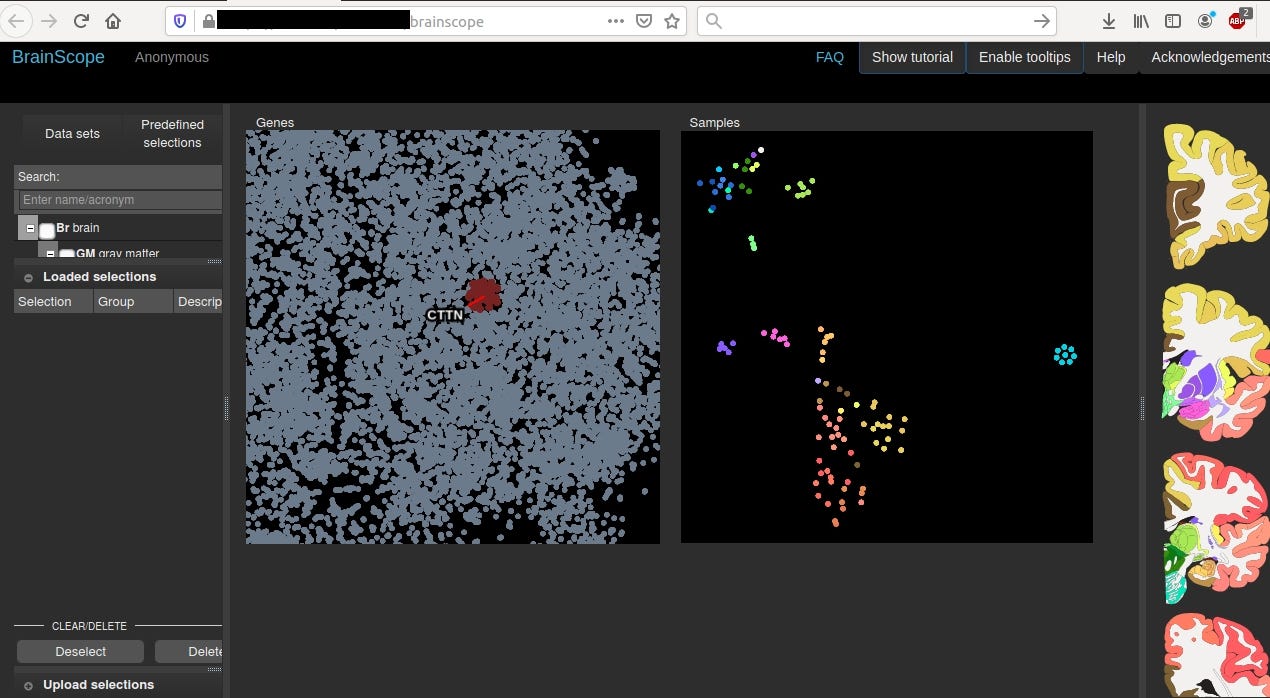

Case #4 Leiden University Medical Center (LUMC), Albinusdreef 2, 2333 ZA Leiden, The Netherlands

BrainScope® is a medical neurotechnology company that is pioneering the assessment of brain injury, including concussion. The company’s innovative BrainScope One system is an easy-to-use, non-invasive, hand-held platform that empowers physicians to quickly make accurate head injury assessments at the point-of-care. https://brainscope.com/

Query: title:BrainScope

This machine is located in net range of “Leiden University Medical Centre”

which is very close to location obtained from geolocation database that Shodan uses.